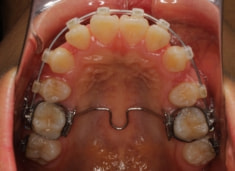

治療後(2年後)